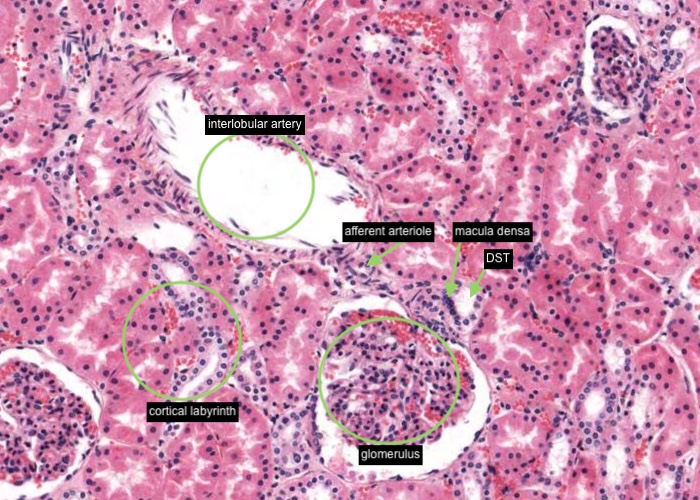

Interlobular arteries give off tiny afferent arterioles which run into the lobule to supply each renal corpuscle. An afferent arteriole enters a renal corpuscle, breaks up into a tuft of capillaries called a glomerulus, and then collects back into an efferent arteriole instead of a vein. This occurs at the "vascular pole". This is a nice image because it also shows part of a glomerulus with the urinary (tubular) pole visible (see more details in the next item). You may see an arteriole, but it will be impossible to tell whether it is afferent or efferent (although there is a slight hint that it is an afferent arteriole because it is adjacent to a distal convoluted tubule - ignore this though for now!). The efferent arteriole runs for only a short distance before breaking up into a second bed of peritubular capillaries, which nourish the proximal and distal tubules and absorb fluid. Even when these capillaries are collapsed you can easily see abundant red blood cells within their lumens between the convoluted tubules.

The distal straight tubule traverses the medulla into the cortex within a medullary ray and aligns itself adjacent to the vascular pole of the renal corpuscle with which it is a component. A clustering of nuclei of epithelial cells lining the distal straight tubule directly adjacent to the afferent arteriole in the vicinity of the vascular pole of the renal corpuscle form the "macula densa".

In the middle of each renal lobule are descending and ascending limbs of the nephron and a collecting duct. Collections of straight tubules and collecting ducts form the medullary ray within the cortex. The renal lobule is a cortical structure and nephrons in the same lobule drain into the collecting duct. Each interlobular artery branches into a number of afferent arterioles which each form a glomerulus, a capillary network and the efferent arteriole.

Each small interlobular artery (sometimes referred to as a "cortical radial artery") originates from the arcuate artery and then travels through the cortical labyrinth (containing the more eosinophilic proximal and the paler stained distal convoluted tubules) between adjacent medullary rays towards the kidney capsule. Some reach as far as the capsule and supply this outer covering of the kidney. An afferent arteriole supplying each glomerulus arises along the path of this interlobular artery or a number may arise from a common branch from the interlobular artery. I think there is an afferent arteriole supplying the glomerulus partly visible in this image because nearby is a macula densa in the wall of a distal straight tubule.